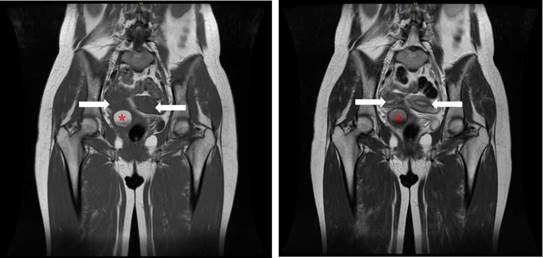

In August 2017, a transvaginal ultrasound showed an increase of approximately 1 cm in mass size; 2 months later, an abdominal ultrasound showed polycystic ovaries, absent right kidney, uterus didelphys, and 20 cm3 of vaginal vault fluid collection. Due to the non-specific characteristics of the mass and its progressive growth, an MRI of the pelvis was performed in October 2018, finding uterus didelphys, multiple small cystic formations in both ovaries, left cervical canal of normal appearance, and right cervical duct with a 35x32x39mm hyperintense space-occupying lesion in T1 sequence and a diffuse and heterogeneous increase of the lesion in T2 sequence (Figure 1). It should be noted that approximately one year elapsed between the performance of the abdominal ultrasound clinical and imaging findings, HWW syndrome was not and the MRI due to administrative delays. Despite these initially considered as a differential diagnosis.

Pelvic MRI in T1 and T2 sequence.

Figure 1: Pelvic MRI in T1 and T2 sequence.

Note: The asterisk indicates a space-occupying lesion (hematocolpos), while the arrow indicates a uterus didelphys.

Source: Document obtained during the study.